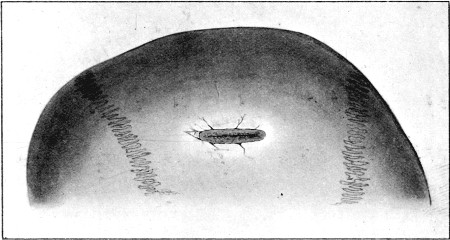

1. Section of Mauser Aperture of Entry To face p. 73

2. Section of Mauser Aperture of Exit 76

25a. Sections of Mauser Entry and Exit Wounds74